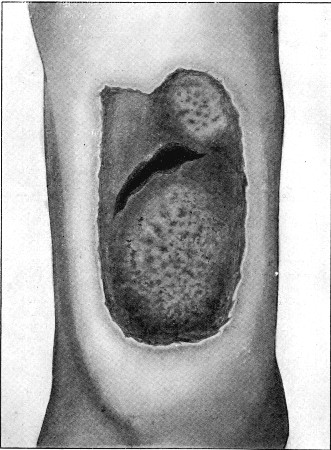

47. Explosive Exit Wound over Fractured Ulna156

48. Explosive Exit Wound over Fractured Humerus158

49. Explosive Exit and Entry Wounds of Legs159